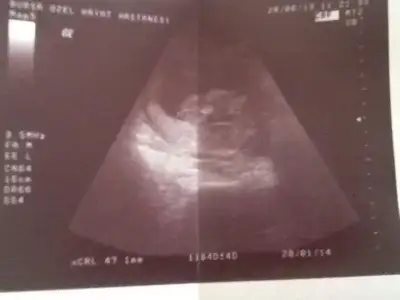

topik terkedilmiş galiba kaç gündür bakıyorum bilen arkadaşlardan kimse yeni ultrson fotolarına yorum yazmamış...

bilenler lütfen yorum yapın.... forum biz yazana kadar işliyordu bizden sonra terkedildi :((((

• $Screenshot_2013-07-02-21-12-05.webp